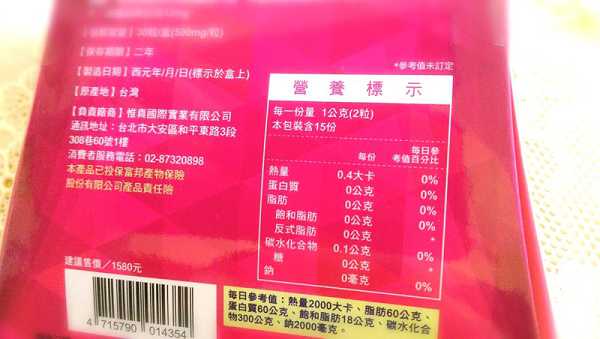

番瀉葉萃取物每日食用限量為12mg以下,

番瀉葉萃取物每日食用限量為12mg以下,

鉻與脂肪代謝有關,有助於控制血液中的膽固醇,並有降低血壓的作用,可以預防高血壓,對降低體重也有不錯的效果。

鉻與脂肪代謝有關,有助於控制血液中的膽固醇,並有降低血壓的作用,可以預防高血壓,對降低體重也有不錯的效果。